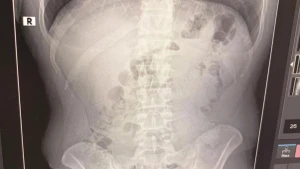

Manset.az xarici mediaya istinadən xəbər verir ki, ilkin ifadələri alınan şəxslər daha sonra Məhkəmə-Tibbi Ekspertiza İnstitutuna göndərilib. Onlardan qan analizi götürülüb.